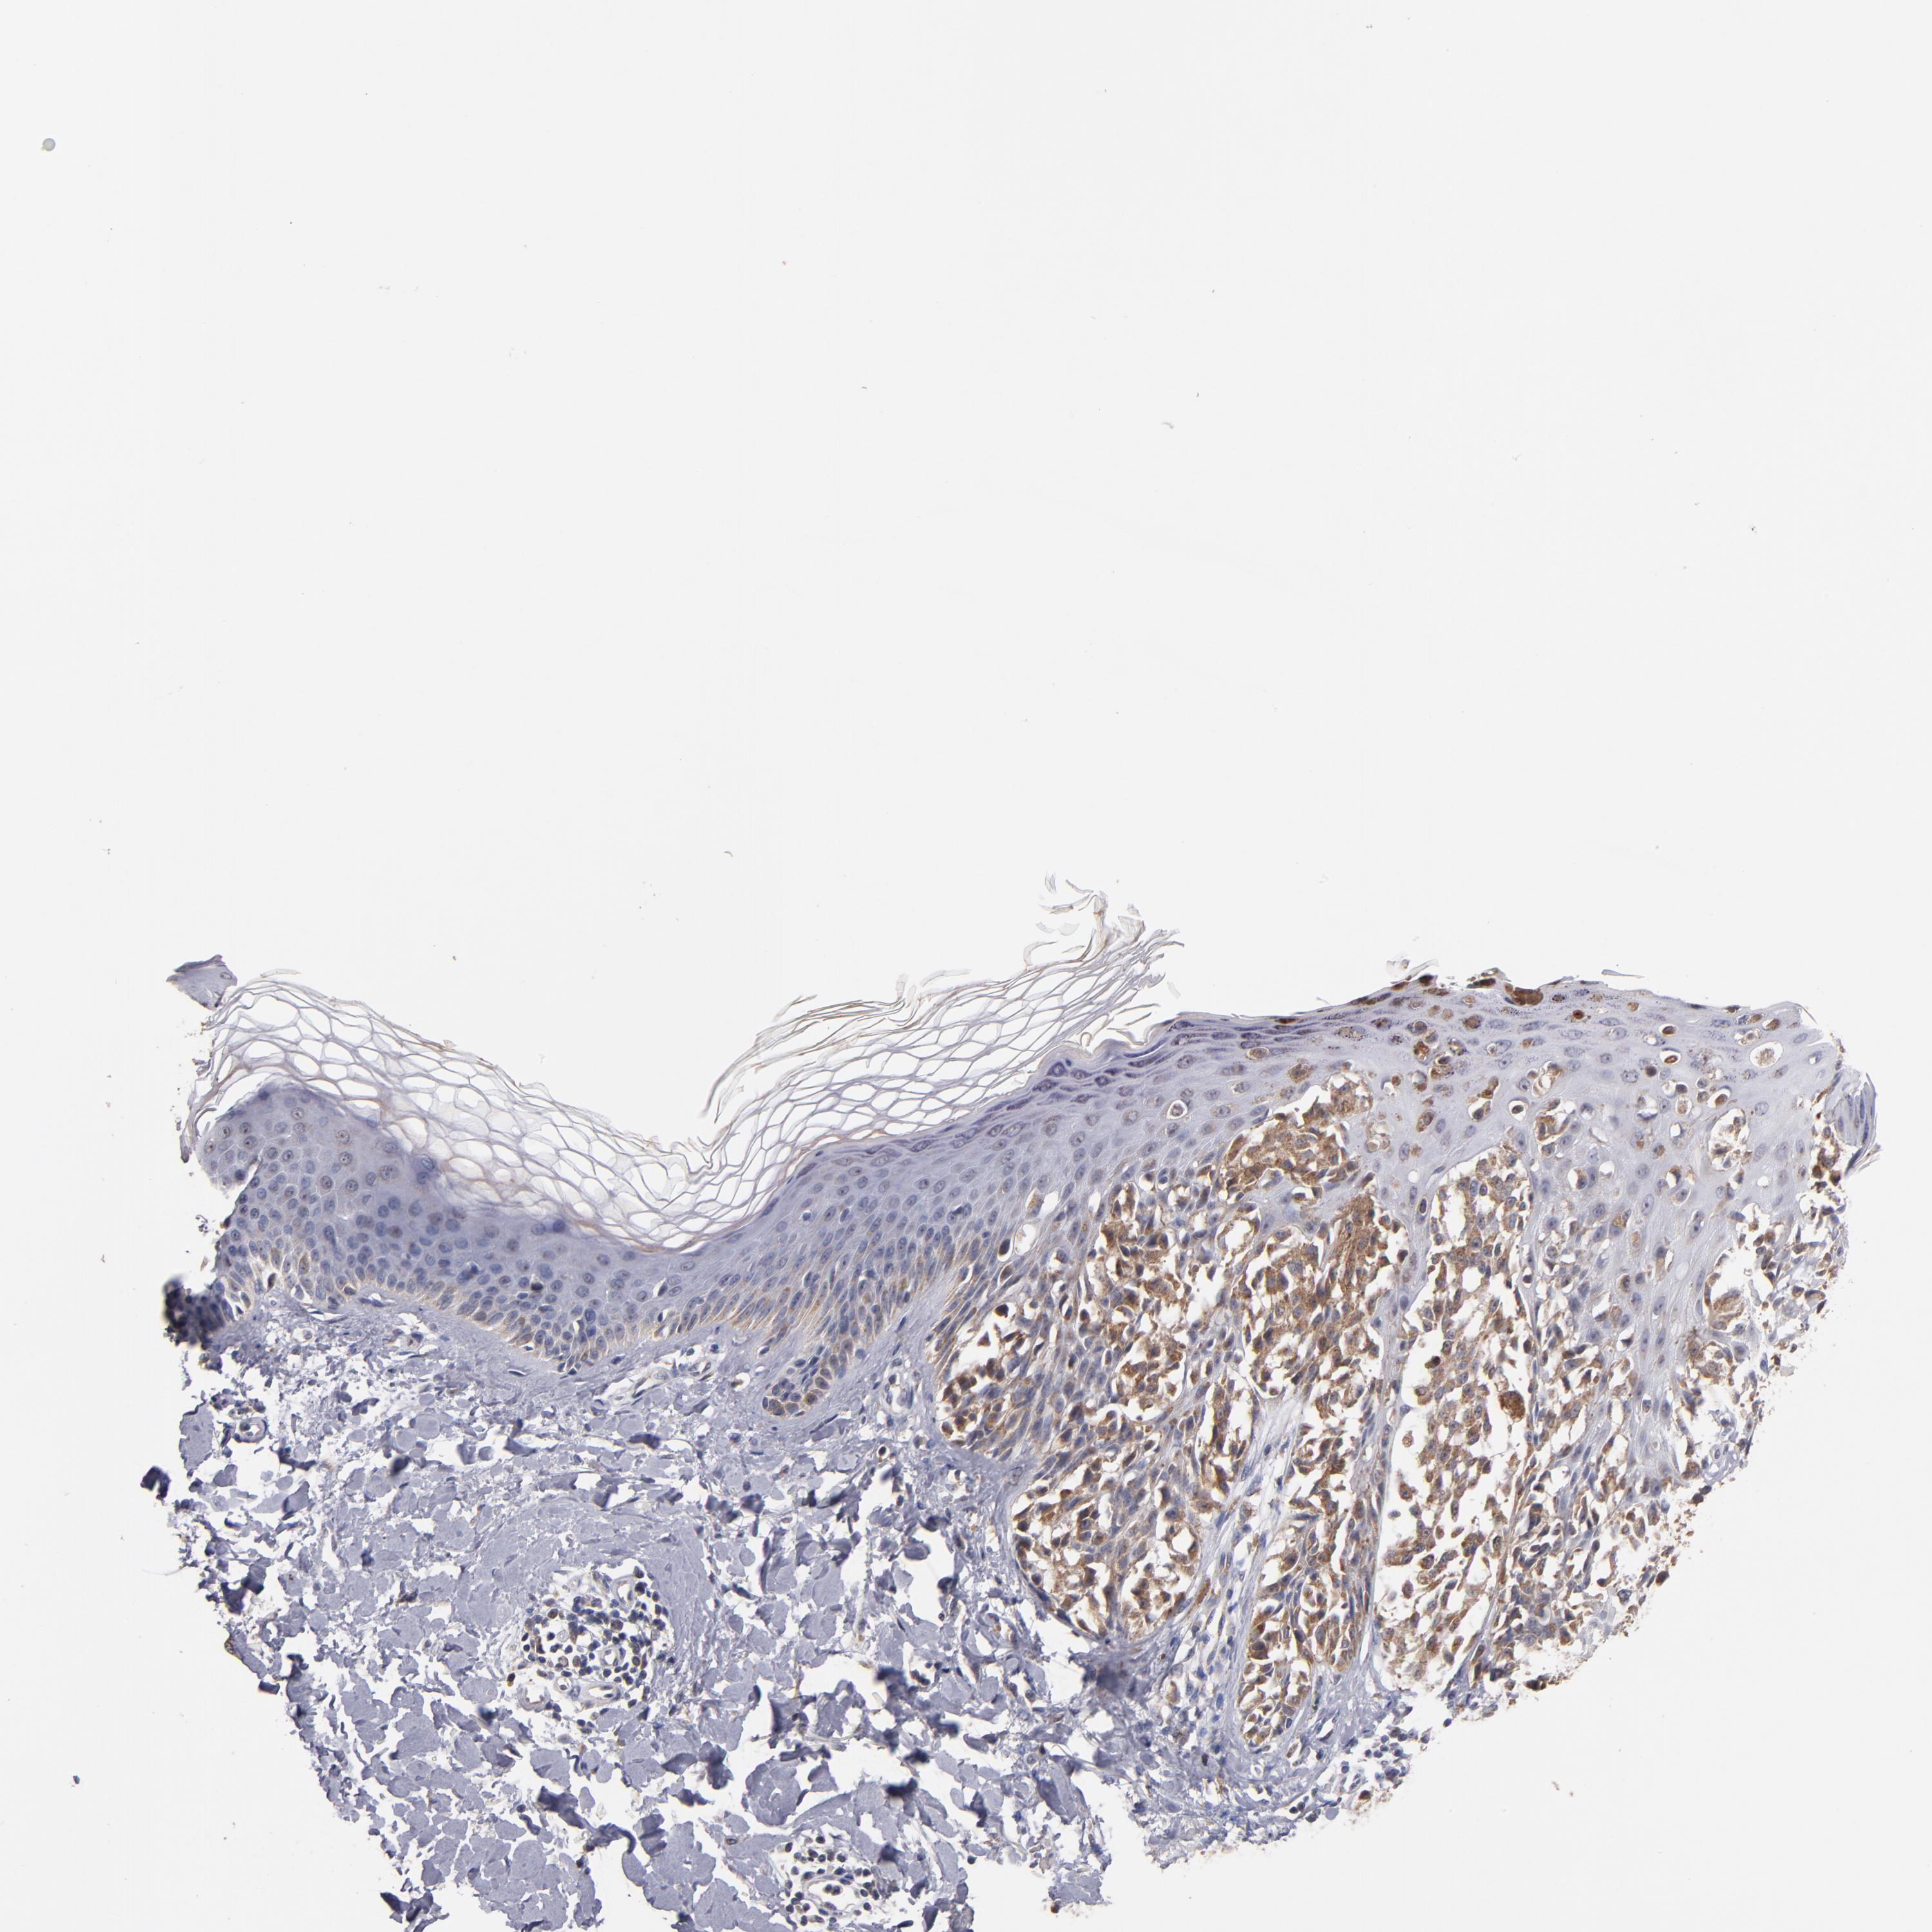

MELANOMA - Protein expressioni

A mouse-over function shows sample information and annotation data. Click on an image to view it in a full screen mode. Samples can be filtered based on level of antibody staining by selecting one or several of the following categories: high, medium, low and not detected. The assay and annotation is described here.

Note that samples used for immunohistochemistry by the Human Protein Atlas do not correspond to samples in the TCGA dataset.

Antibody stainingi

Antibody staining in the annotated cell types in the current human tissue is reported as not detected, low, medium, or high, based on conventional immunohistochemistry profiling in selected tissues. This score is based on the combination of the staining intensity and fraction of stained cells.

Each image is clickable and will lead to virtual microscopy that enables deeper exploration of all samples and also displays staining intensity scores, fraction scores and subcellular localization as well as patient and tissue information for each sample.

Antibody HPA001825

Antibody CAB003857

Staining

High

Medium

Low

Not detected

Intensity

Strong

Moderate

Weak

Negative

Quantity

>75%

75%-25%

<25%

None

Location

Nuclear

Cytoplasmic/membranous

Cytoplasmic/membranous,nuclear

Malignant melanoma, NOS

Malignant melanoma, Metastatic site